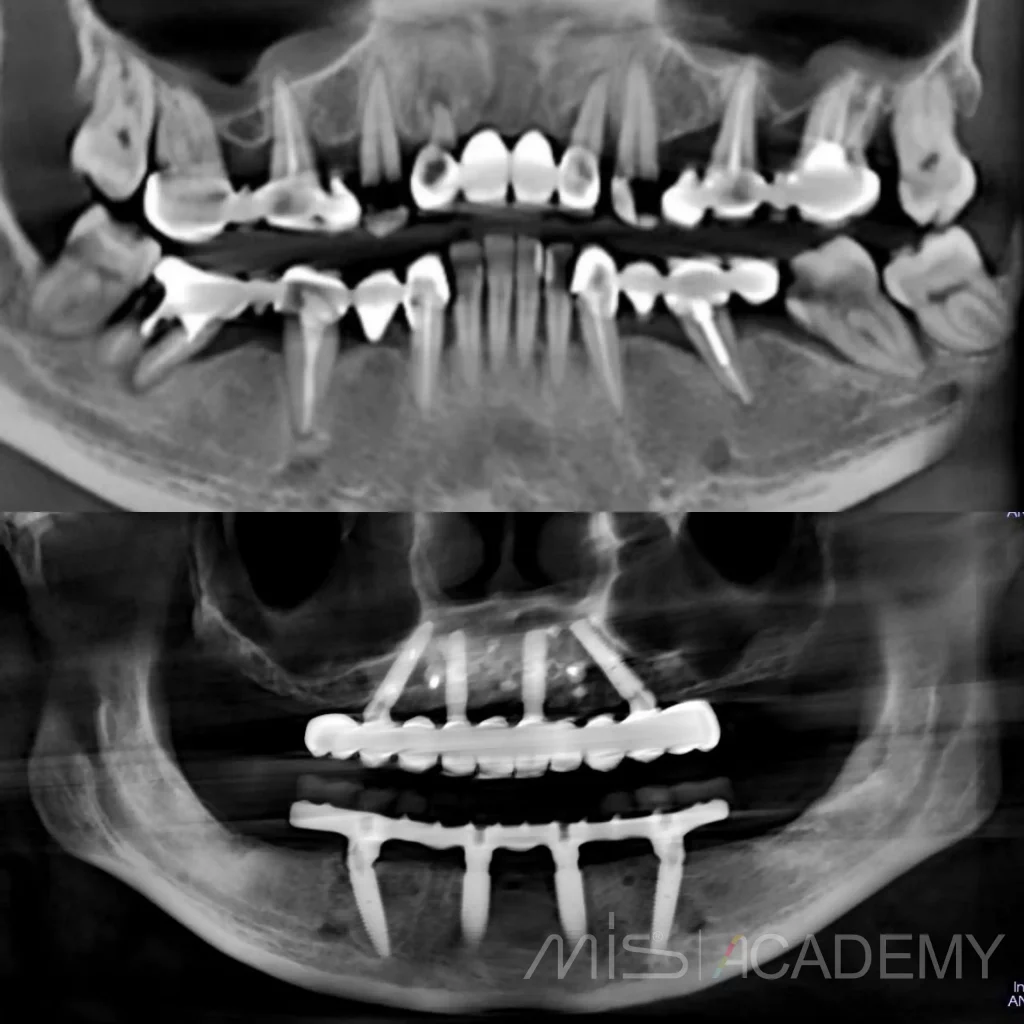

Клинический случай НКР верх фронт и последующие АО4 верх-низ.

На сегодняшний день возможно реализовал бы всё без НКР и возможно даже в FP1 (или аутоламинами, сократили бы сроки), но есть моменты по мягким тканям + вернусь ещё на устранение рецессии в области MU 24.